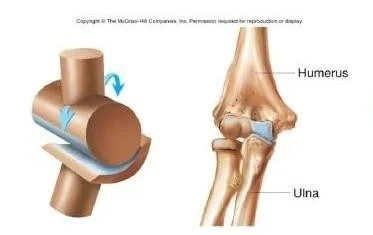

Hinge(knee)

- Humerus

- Ulna